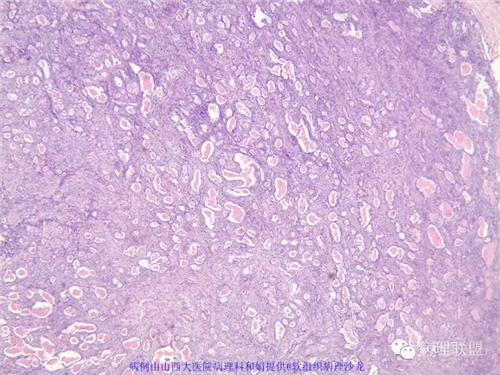

M,57岁,右膝关节外侧皮下肿物10余年,活动度好。

本例形态学上是非常典型的双相型滑膜肉瘤,滑膜肉瘤临床上大部分表现为生长缓慢的肿瘤。以青壮年多见,主要发生于四肢大关节附近,也可见于其他少见部位,如肺、肾等实质器官,形态学分为5种类型:单相纤维型、单相上皮型、双相型、低分化梭形细胞型和小细胞型。有文献报道个别患者有长达20年的病史。